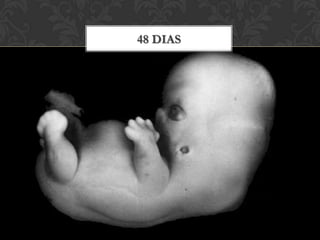

48 dias